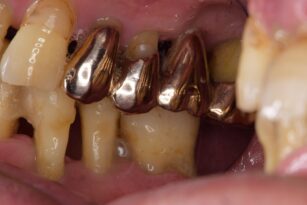

金属が気になる 30代 女性 セラミックインレーの症例

前歯の色が気になる 40代 男性 ラミネートべニア、レジン修復の症例